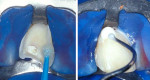

No alterations in the periodontal and bone tissues were observed in the radiographic examination (Figure 2). As the first clinical step, the coronal fragment and remaining root portion were cleaned with rubber cup pumice prophylaxis. There was a small area of pulpal exposure, which was partially curetted (Figure 3) and received a dressing with a commercially prepared antibiotic corticosteroid (Otosporin®, GlaxoSmithKline, www.gsk.com) for 5 minutes followed by direct pulpal capping with calcium hydroxide p.a. and a calcium hydroxide-containing cement (Hydro C, DENTSPLY, www.dentsply.com). A full-thickness flap was elevated to provide better access to the fracture line, as well as to permit the correct placement of a rubber dam and provide a clean, dry operative field. Flap elevation revealed a fracture margin ending in a 0° angle and an adequate adaptation of the coronal fragment to the remaining root portion (Figure 4). The coronal fragment and remaining root portion were then etched with 37% phosphoric acid, rinsed thoroughly, and gently air-dried. The coronal fragment was re-attached to the root remnant using an adhesive restorative technique with an etch-and-rinse adhesive system (Prime & Bond 2-1®, DENTSPLY) and a light-cured microhybrid composite resin (TPH®, DENTSPLY) (Figure 5). The restoration of the fractured crown was completed at the cervical third with resin-modified glass ionomer cement (GC Fuji II LC, GC America Inc., www.gcamerica.com) (Figure 5).

All restored surfaces were finished with fine-grain diamond points and polished with fine and superfine grain polishing discs (Sof-Lex™ Pop-On, 3M ESPE, www.3MESPE.com). The flap was repositioned and sutured. Antibiotic therapy (amoxicillin 500 mg, 3 times/day) was started and maintained for 7 days. The use of 0.12% chlorhexidine oral rinse twice daily for 7 days was prescribed. After 15 days, a groove extending from the buccal to the palatal side of the tooth was prepared with a No. 1302 round diamond bur at high speed along the fracture line (Figure 6) and was restored with composite resin in order to mask the union between the fragments and improve esthetics.